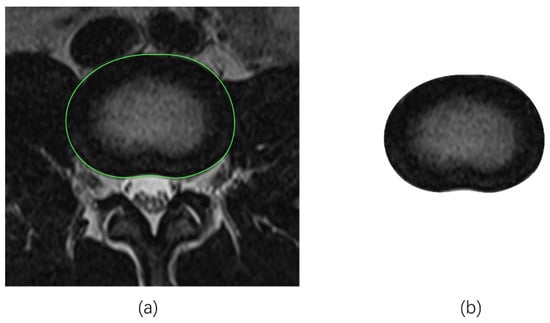

2.2.1. Tracing the IVD Contours

2.2.2. Tracing the NP Contours

- Manual tracing (MT)